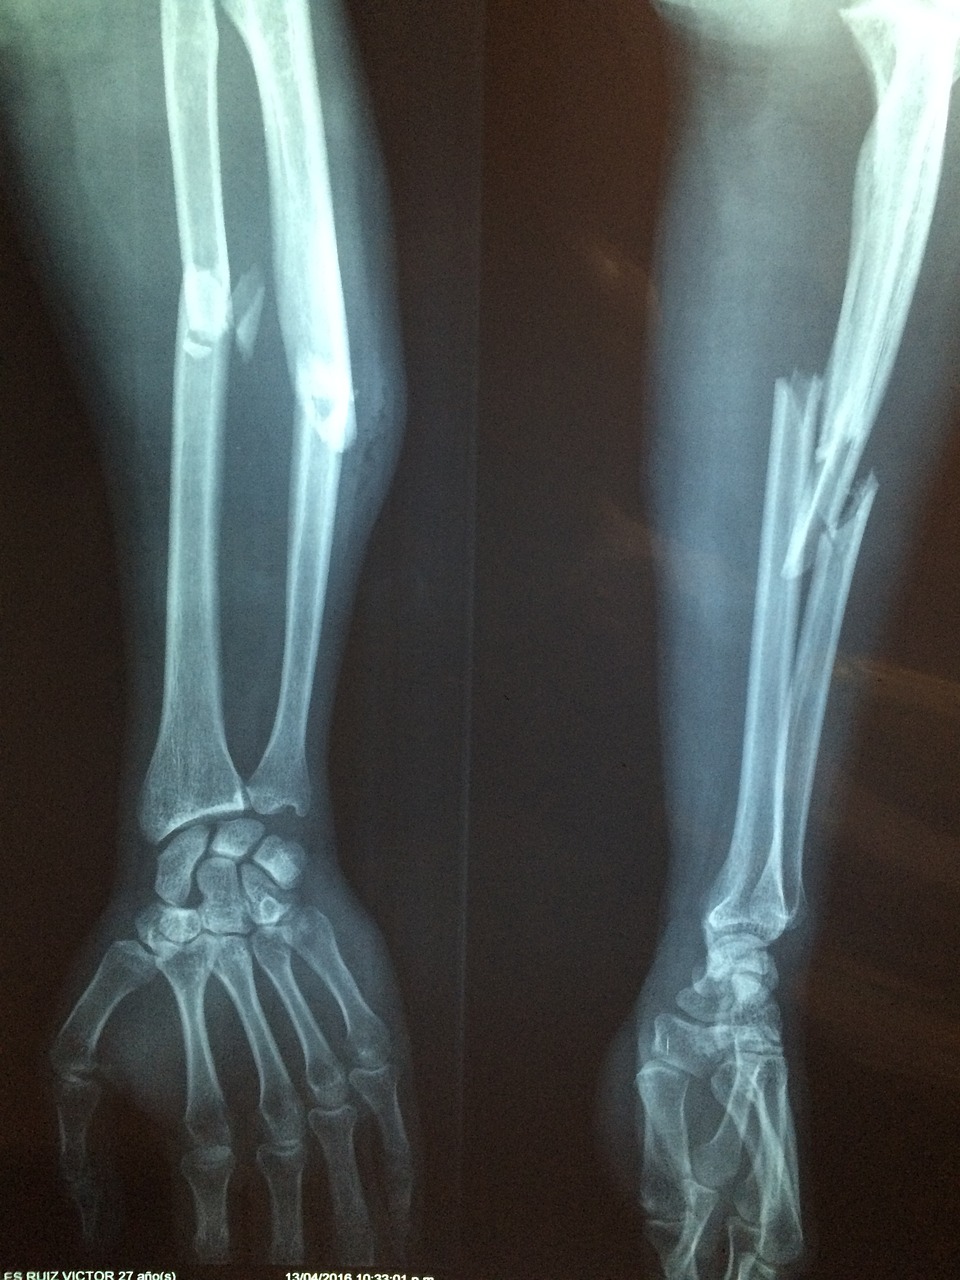

* 골절 : 골다공증이 있는 경우 작은 충격에도 쉽게 골절이 발생할 수 있습니다. 골절이 발생한 부위는 통증, 붓기, 변형 등의 증상이 나타날 수 있습니다.

![]() |